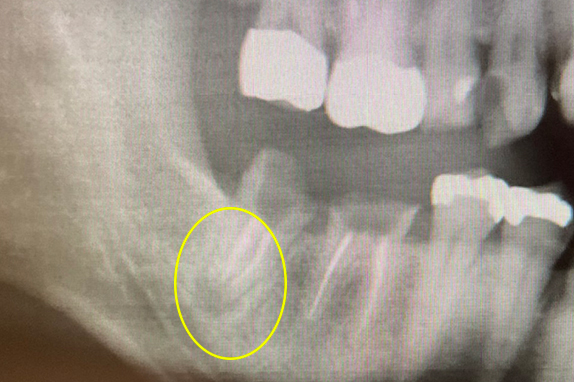

CASE 07 マイクロエンド(精密根管治療)+歯根周囲掻爬(歯周外科)

-

- 主訴

- 歯ぐきがよく腫れる(10代女性)

-

- 回数期間

- 7回 約1年半

-

- 治療法

- マイクロエンド(精密根管治療)、歯根周囲掻爬(歯周外科)

-

- 治療費用

- 約35万円(税抜)

歯ぐきがよく腫れる主訴で来院。レントゲン写真の術前を見ると大きな影が確認できます。この部分に嚢胞(のうほう)がある状態です。マイクロエンドと歯根周囲掻爬(歯周外科)をすることで改善したケースです。

<リスク・副作用>

治療後は痛み、腫れ、痺れなどの副作用が生じる場合があります。症状が再発する可能性があります。